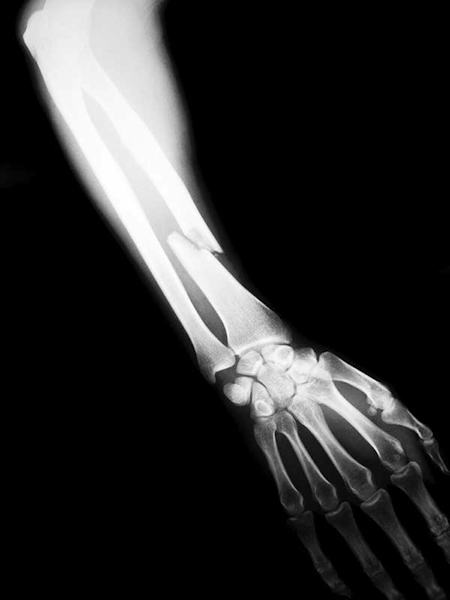

According to a 2012 report by the U.S. Consumer Product Safety Commission’s National Electronic Injury Surveillance System (NEISS), damages to bones are the most common injuries among athletes aged 25 to 40 who play basketball, soccer, football, and baseball. The knees, ankles, and fingers were found to be the most likely casualties.

The results of several long-term trials suggest that having more strontium in your system may boost bone mineral density, and thus your bones’ resilience. This makes strontium valuable to athletes who participate in high-impact sports, such as those listed above (as well as mixed martial arts, where the impact from hitting pads, the mat, and an opponent’s face can take its toll). It’s also critical for older individuals who face bone health problems associated with aging. Below are some of the key findings in support of strontium.